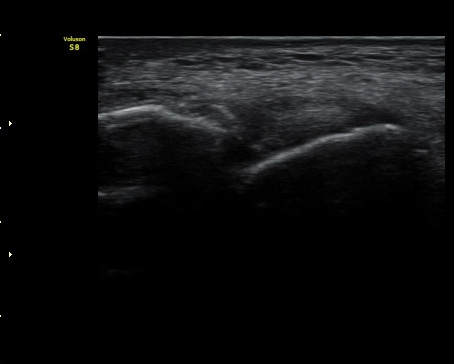

3ÁÖ ÈÄ ÃßÀû°Ë»ç¿¡¼­ ¹Ú¸®µÈ°ñÆíÀÌ °üÂûµÇ°í ÀδëÀÇ Àú¿¡ÄÚ ºÎÁ¾Àº ¾à°£

Áõ°¡µÈ ¼Ò°ßÀ» º¸ÀÓ(±×¸² 3, 4).